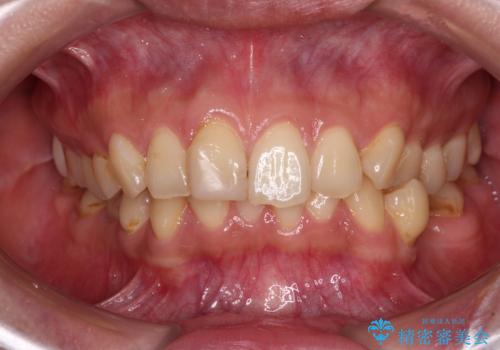

- 前歯のデコボコと深い咬み合わせを気にして来院された患者様です。

骨格的に上顎骨がやや前方にあり、それが原因で下顎前歯が隠れるほどのディープバイトになっている状態でした。

補助装置を用いて、上顎大臼歯を積極的に後方移動させながら、ディープバイトを改善していくこととしました。

強い咬合力に抵抗するため、上下ともに表側のワイヤー装置にて矯正治療を行うこととしました。